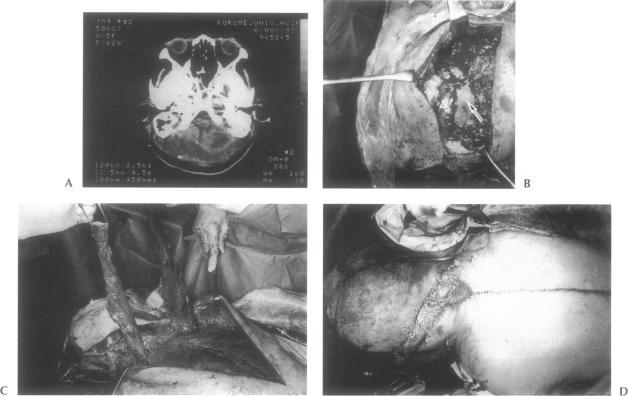

Two patients developed an epidural abscess in the posterior cranial fossa following tumor dissection from the occipital region of the head and underwent surgical treatment. After debridement of necrotic and infectious tissues inside the abscess was performed, the empty cavity was filled and the tissue defect was reconstructed by using a trapezius muscle flap or a trapezius musculocutaneous flap. Both patients had good clinical results, and their abscesses were healed. The trapezius muscle flap and trapezius musculocutaneous flap were quite useful in the treatment for epidural abscess in the posterior cranial fossa.